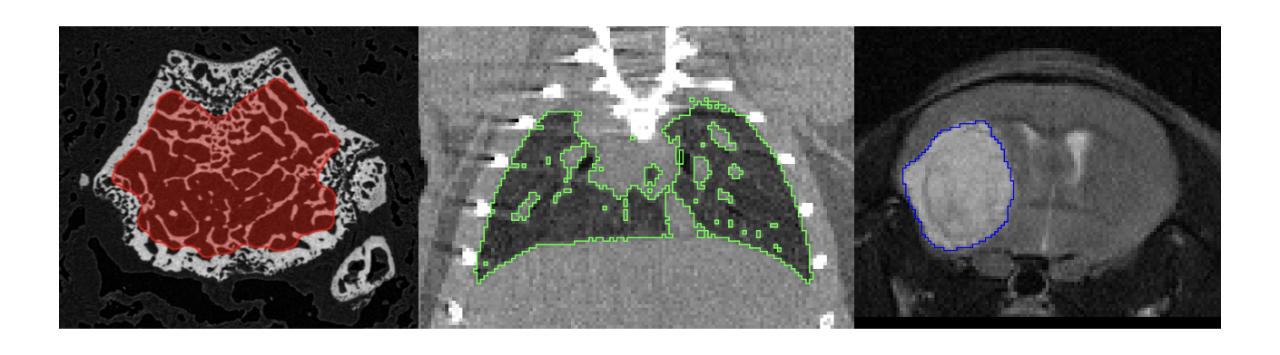

pmod’s tools provide comprehensive workflows for post-processing and quantification of imaging data for fundamental oncology research, development of radiotracers and theranostics, and in clinical research studies. Imaging scientists can trust pmod to reproducibly read their data, interpret the meta-data/units and help users calculate statistics such as SUV for their studies and publications.

• Multimodality segmentation tools – comprehensive semi-automated and manual tools for precision and reproducibility

• Full access to metadata – ensure accurate calculation of Standard Uptake Value and other key statistics

• Flexible switching between 3D and 4D datasets – direct output of time activity curves